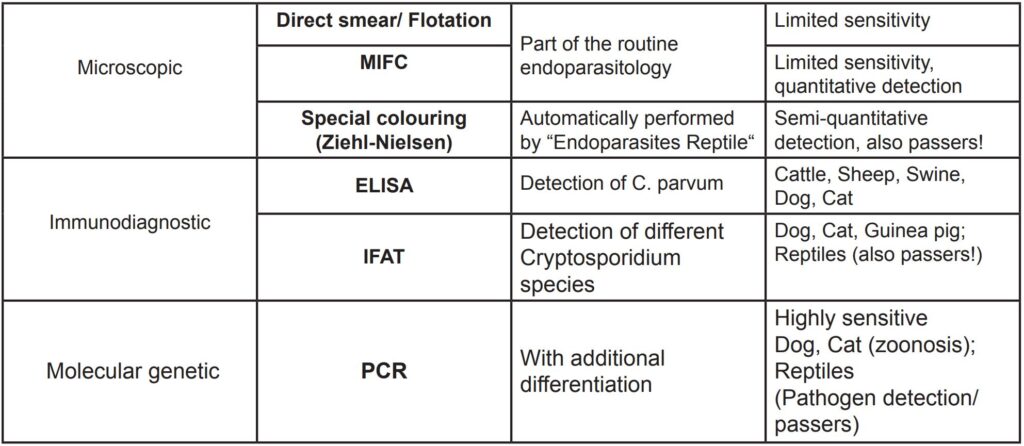

- Tab. 1: Cryptosporidium diagnostics

For laboratory diagnostics, several methods for detection are available. Already on a microscopic examination after specific enrichment (MIFC) oocysts can sometimes be found. Like all parasitological faeces examinations the sensitivity is limited to about 60%.

Reptile faeces samples are additionally coloured (modified Ziehl-Nielsen stain) before microscopy to increase the detection rate. In cattle, it is recommended to use the ELISA test for detection of C. parvum.

Immunofluorescence includes a wider range of Cryptosporidium species and is therefore more suitable for dogs, cats as well as small rodents (guinea pigs, C. wrairi).

In reptiles, a positive IFAT result cannot distinguish between pathogenic intestinal pathogens and passers.

Here the PCR test with connected differentiation can provide very sensitive and accurate pathogen detection.

Cryptosporidium diagnostics: